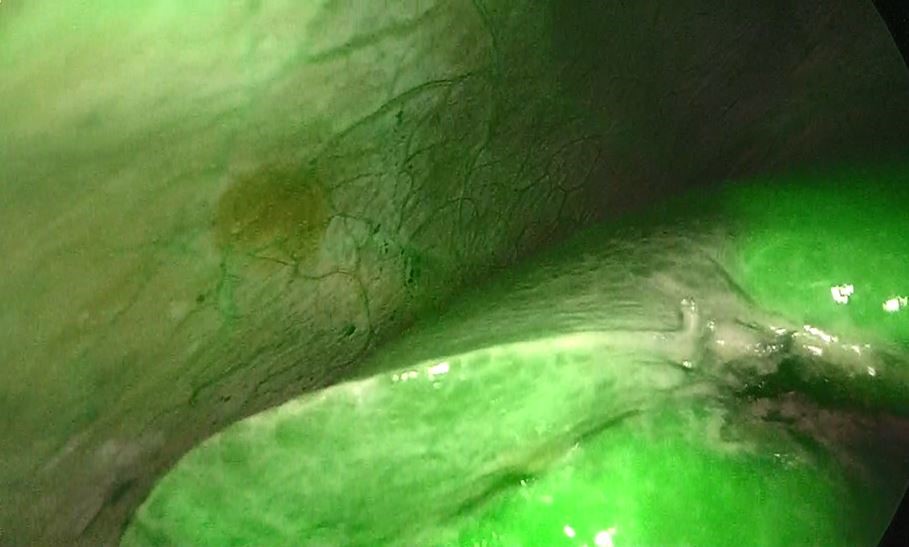

また、正確な肝切離を行うために、蛍光カメラも併用しながら手術を行っています(図3、4)。